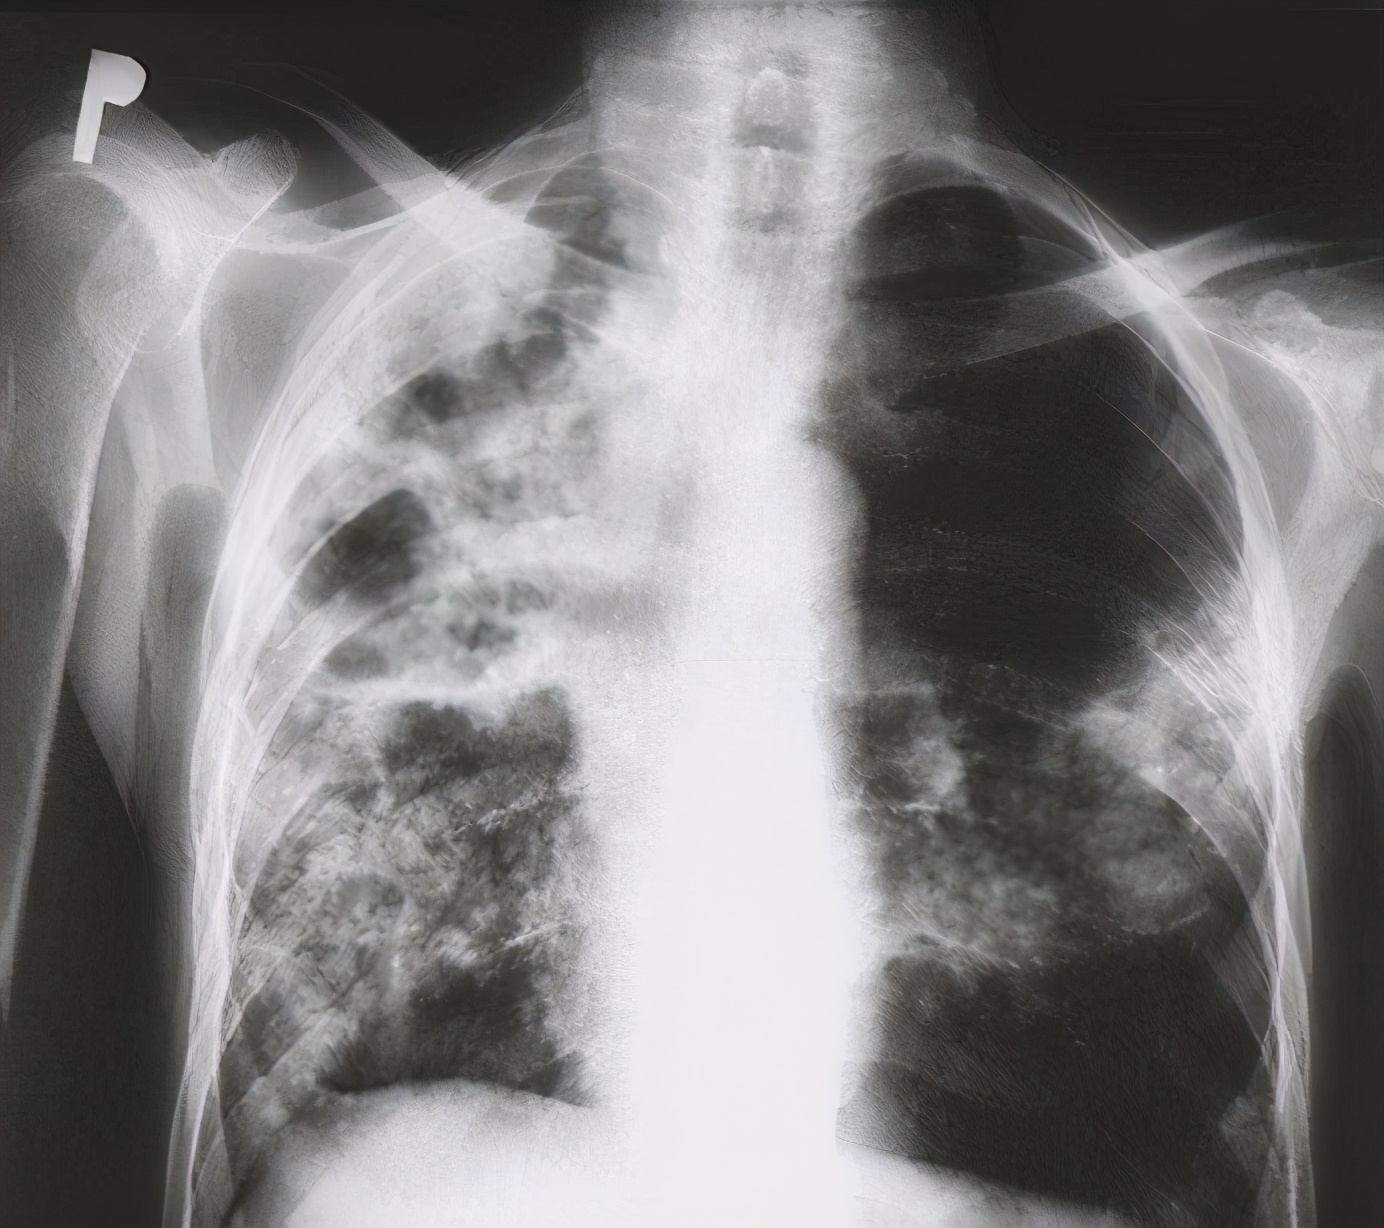

再次来到医院检查核酸和抗体还是阴性的,细心的医生询问了病史,做了胸部放射线检查,最后建议患者去传染病医院看一下。

在我国县级以上的地区都会设有结核病防治中心,在这里,只要是可疑肺结核的患者,都会免费做胸片和痰涂片等检查。